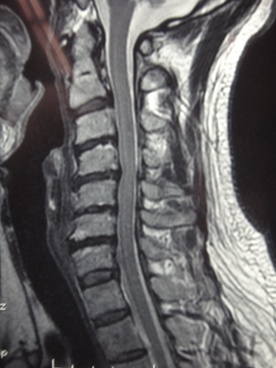

症状と画像所見及び神経学的所見の一致する旨の主治医の意見書の作成により、12級13号が認められた事案

40代男性 乗用車に乗車中、4トントラックから追突を受け、さらに前2台に追突した計4台が絡む玉突き事故により、頚椎捻挫と診断され、左頚部・左肩から上肢(親指にかけて)の痛み・しびれ感等の後遺障害が残存した事案です。

MRI画像上C5/6椎間板ヘルニア及び黄色靭帯の肥大化、椎間関節部の骨棘の形成による、前後方からの脊髄神経の圧迫が認められます。

神経学的検査結果は、左手関節伸展筋4、左C6領域の感覚低下、腕橈骨筋腱反射低下、Jachkson・Spurling左陽性で、症状と一致しました。

被害者請求時は14級9号の認定に留まりましたが、画像所見及び神経学的検査結果が症状を裏付けている旨の主治医の意見書を提出し、異議申立てを行った結果、「提出の頚部画像上、第5/6頚椎で左神経根の圧迫所見が認められ、神経学的にも左上肢の腱反射等の異常所見が認められること等から、他覚的に神経系統の障害が証明されるものと捉えられる」として12級13号が認定されました。